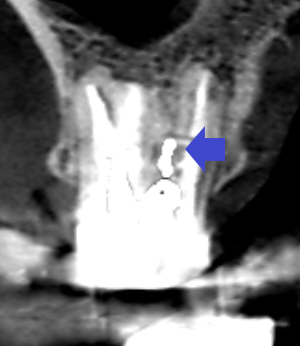

上顎第一大臼歯の冠状断のCT画像です。

赤い矢印の先の近心頬側根に膿の影がみられます。近心頬側根には、青い矢印の先に黒い線が認められ、未治療の根管があります。近心頬側根の膿は未治療の根管が原因と思われます。